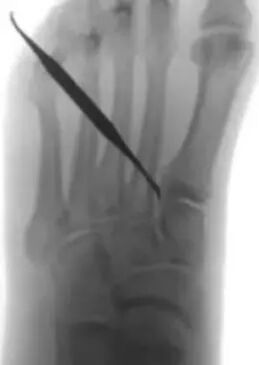

点式复位钳复位。从第二跖骨基部插入到内侧楔骨的 1.6 mm 导针。使用 3.5 毫米的空心钻头钻内侧楔骨。